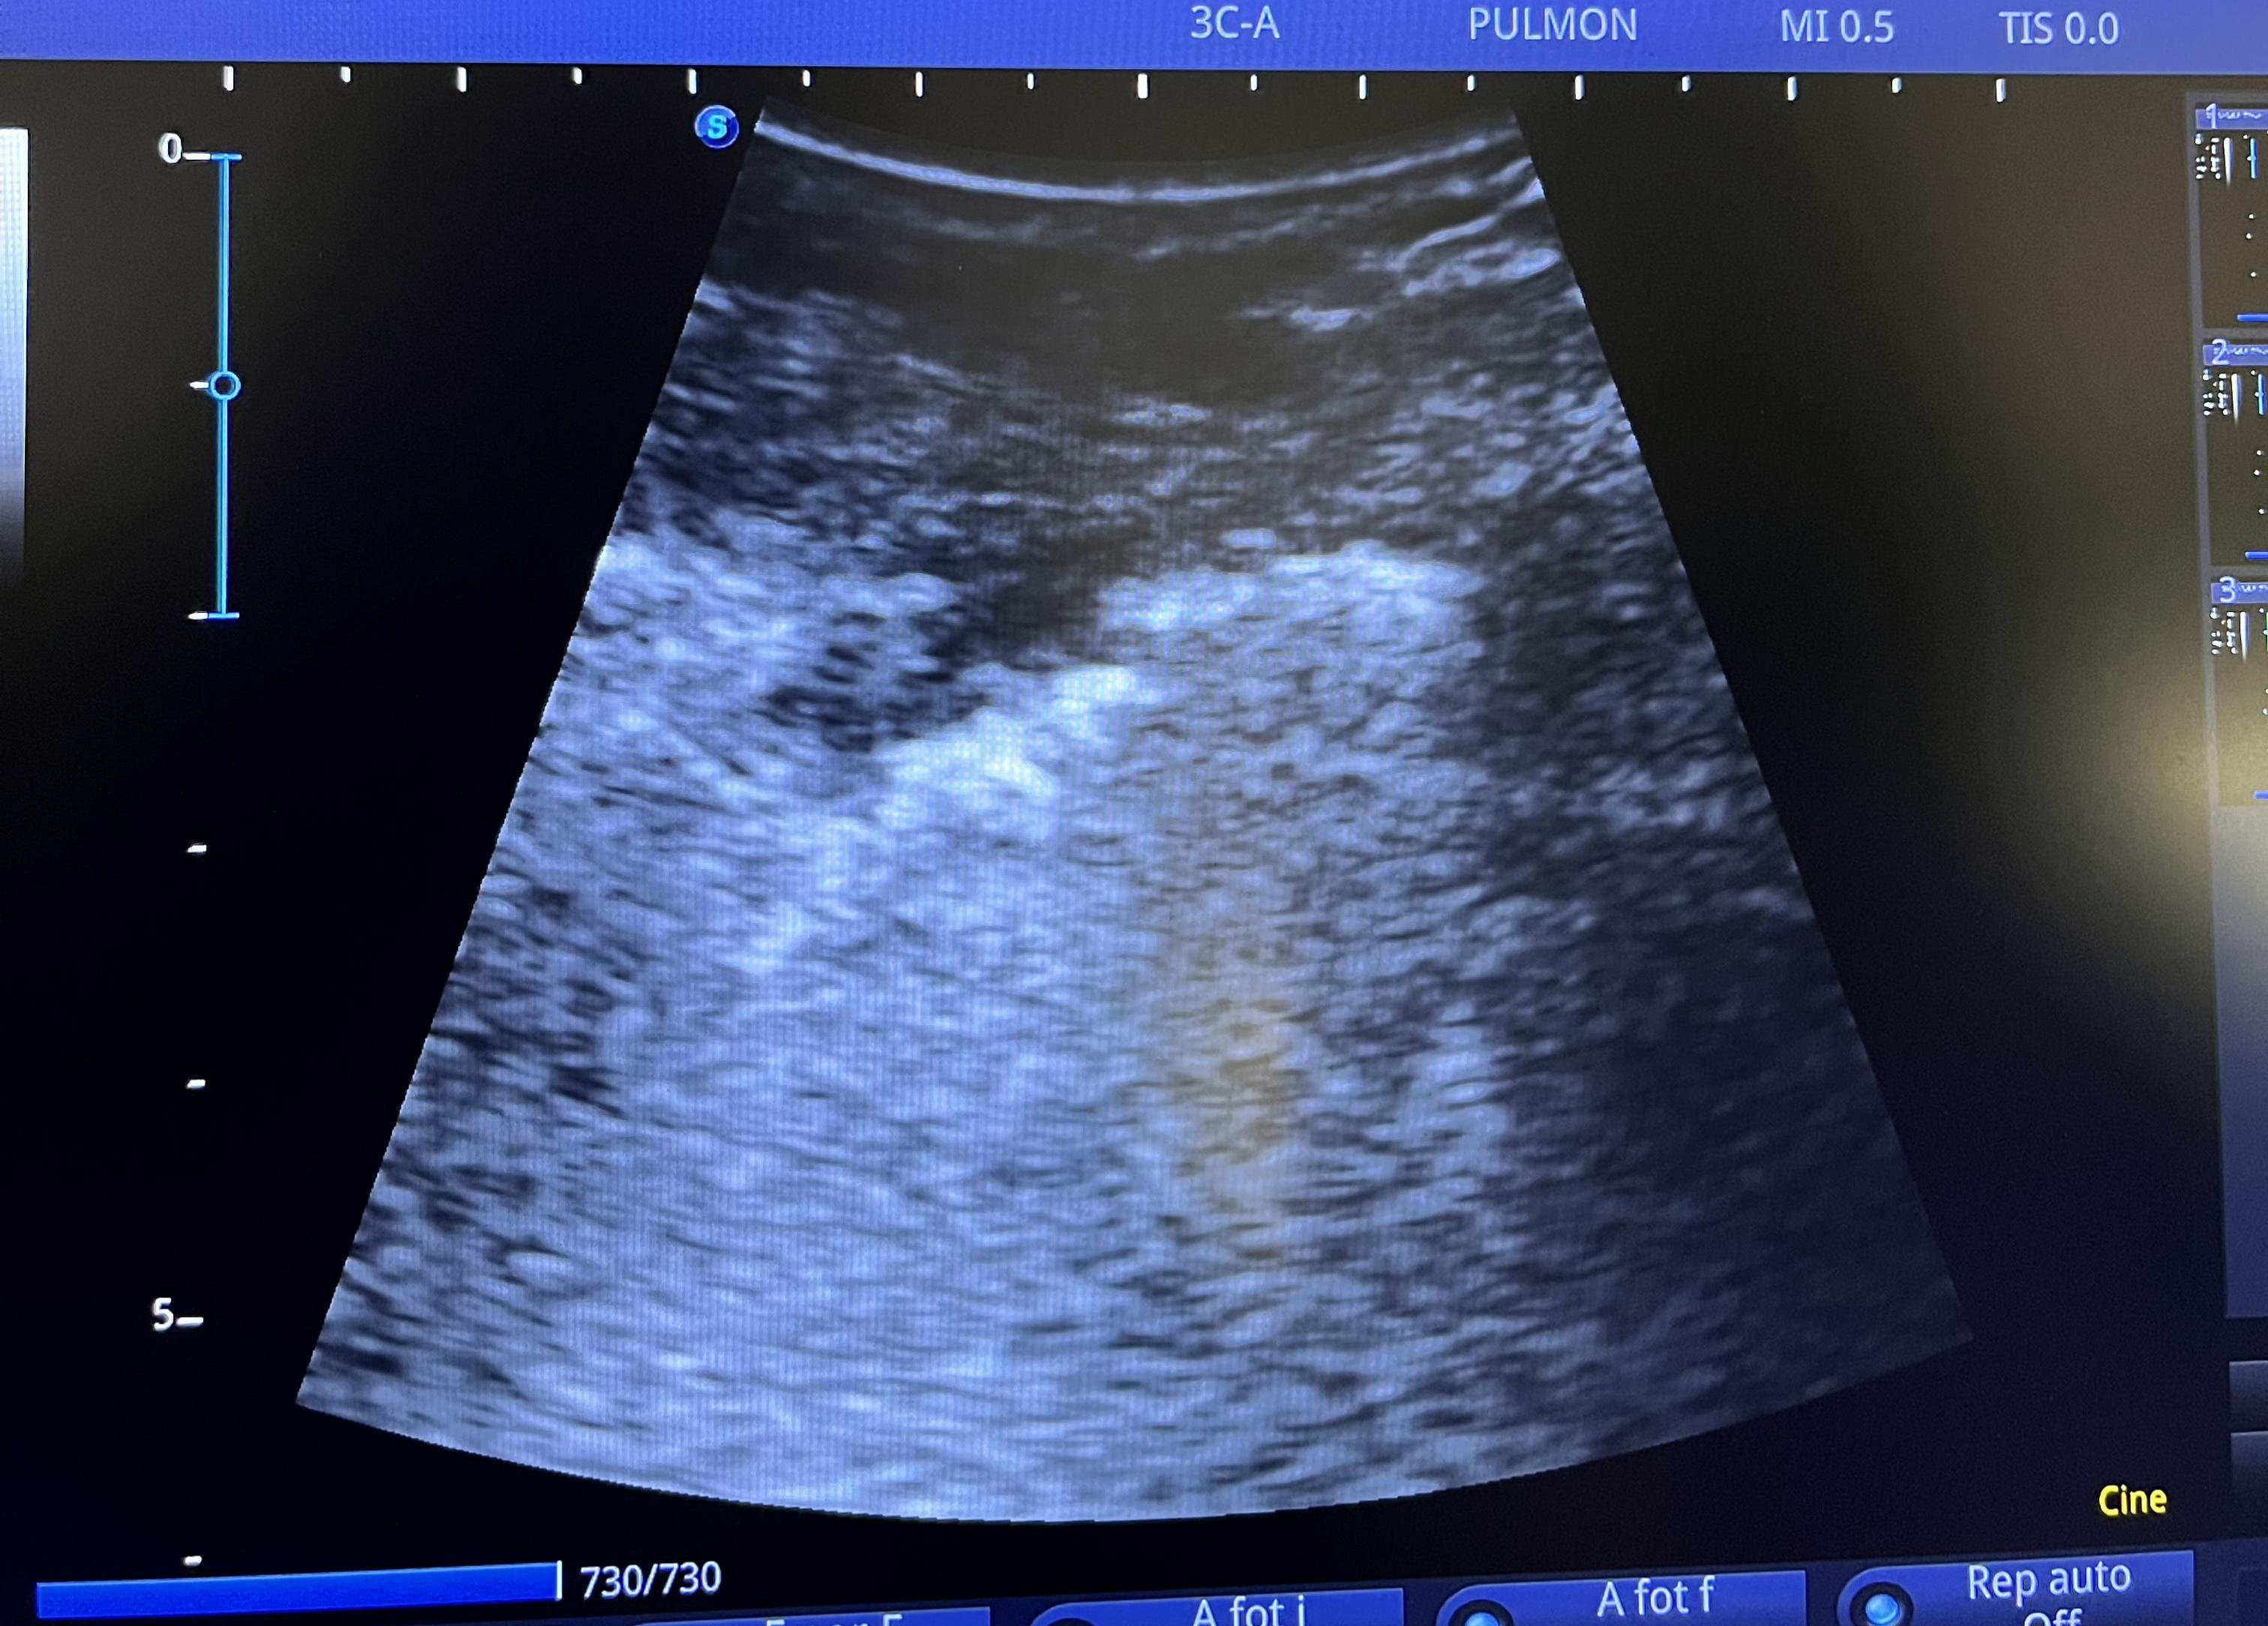

Se realiza ecografía pulmonar a pie de cama para completar estudio.

En la ecografía a pie de cama se observa condensación subpleural de unos 2 x 3 cm en base pulmonar derecha, próxima a seno costofrénico. Se observan también abundantes líneas B subpleurales en dichos campos pulmonares, algunas con imagen en «cola de cometa».